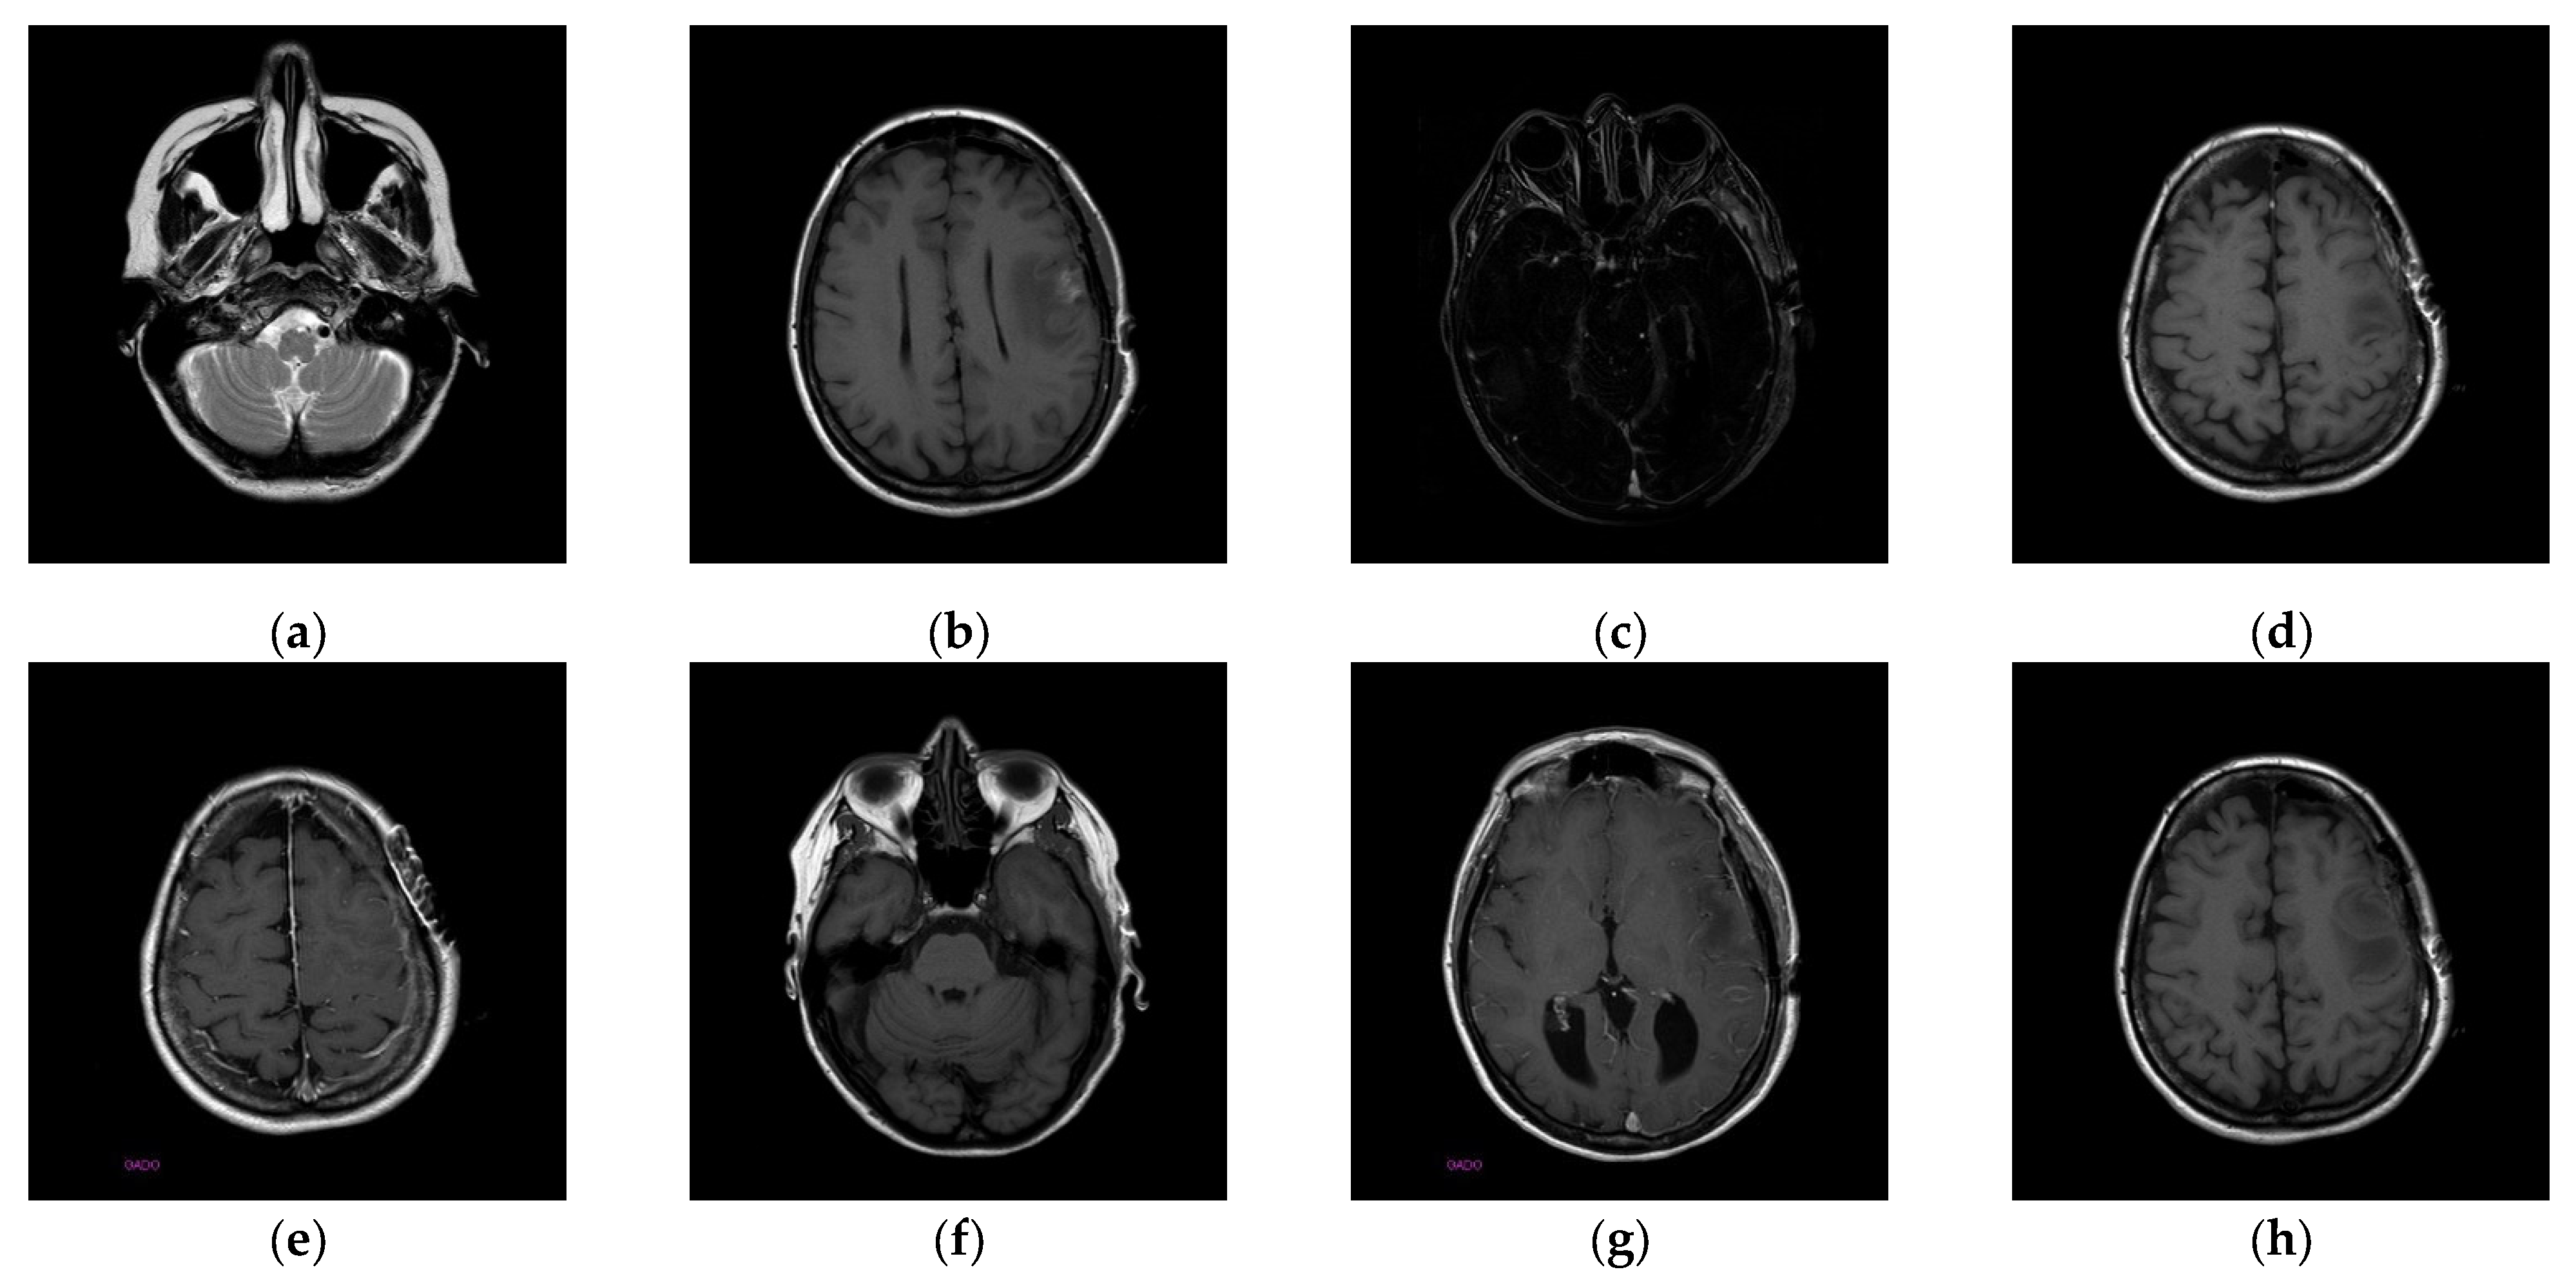

The experiments were conducted on two systems. The first system ran on Ubuntu 22.04, equipped with an Intel i7-9700KF CPU @ 3.60GHz (8 cores), an Nvidia GeForce RTX 3090 GPU, 32 GB of RAM, and Pytorch (https://pytorch.org/) for the experimentation. The second system, called the Type 1 device, is a notebook with an Intel(R) Core (TM) i7-10510U CPU @1.80 GHz 2.30 GHz, 16.0 GB RAM, 64-bit Windows operation system, and GPU MX 250. The third system, called the Type 2 device, is a notebook with an 11th Gen Intel(R) Core(TM) i5-11400H @ 2.70 GHz 2.69 GHz, 24.0 GB RAM, 64-bit Windows operation system, and GPU Nvidia GeForce 3060. The second system is a notebook that was released around 2019 or early 2020. The third system is also a notebook that was released in early 2021. The two systems were used to simulate resource-constrained environments. Different medical and test images were used as the test images to evaluate the performance of our proposed scheme and to make comparisons between our scheme and Qin et al.’s scheme [20]. In the first experiment, eight medical images, which are MRI scans of the brain, were randomly selected from the Osirix database [21] as test images and are presented in Figure 10 to demonstrate the performance of our proposed scheme in detail. In the second experiment, one hundred medical images, which are also MRI scans of the brain, were randomly selected from the Osirix database [21] to form Dataset 1 and Dataset 2, as shown in Figure 11, to prove the stable performance of our proposed scheme. In the third experiment, six general grayscale images, sized 512 × 512, demonstrated in Figure 12, were used to compare with those offered by Qin et al.’s scheme [20]. The logo depicted in Figure 13a was used as the watermark for the first and the second experiments and Figure 13b was used as the watermark for the third experiment.

Figure 10.

Eight medical test images. (a) 10.png; (b) 11.png; (c) 14.png; (d) 16.png; (e) 19.png; (f) 26.png; (g) 31.png; (h) 57.png.